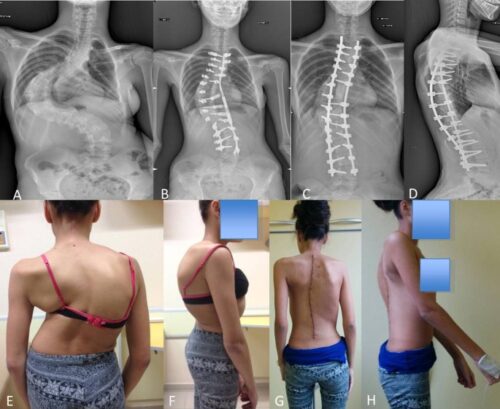

متى لا يُوصى باستخدام الحزام في علاج الجنف؟

رغم فعاليته في كثير من الحالات، إلا أن الحزام الطبي غير مناسب في بعض الظروف، منها:

المرضى الذين أكملوا نموهم العظمي بالكامل.

الحالات التي يتجاوز فيها الانحناء 45°، حيث يصبح الحل الجراحي أكثر فاعلية.

هل يمكن تجنّب الجراحة باستخدام الحزام فقط؟

في كثير من الحالات، نعم. تشير الدراسات إلى أن العلاج بالحزام يقلل من احتمال الحاجة إلى الجراحة، خاصة عند استخدامه مبكرًا مع التزام كامل بخطة العلاج.

خلاصة: متى تستخدم الحزام لعلاج الجنف؟

استخدم الحزام في حالات الانحناء من 25° إلى 40°، خاصة في مراحل النمو المبكر.

تأكد من عدم وجود تحدب صدري حقيقي أو حالات متقدمة فوق 45°.